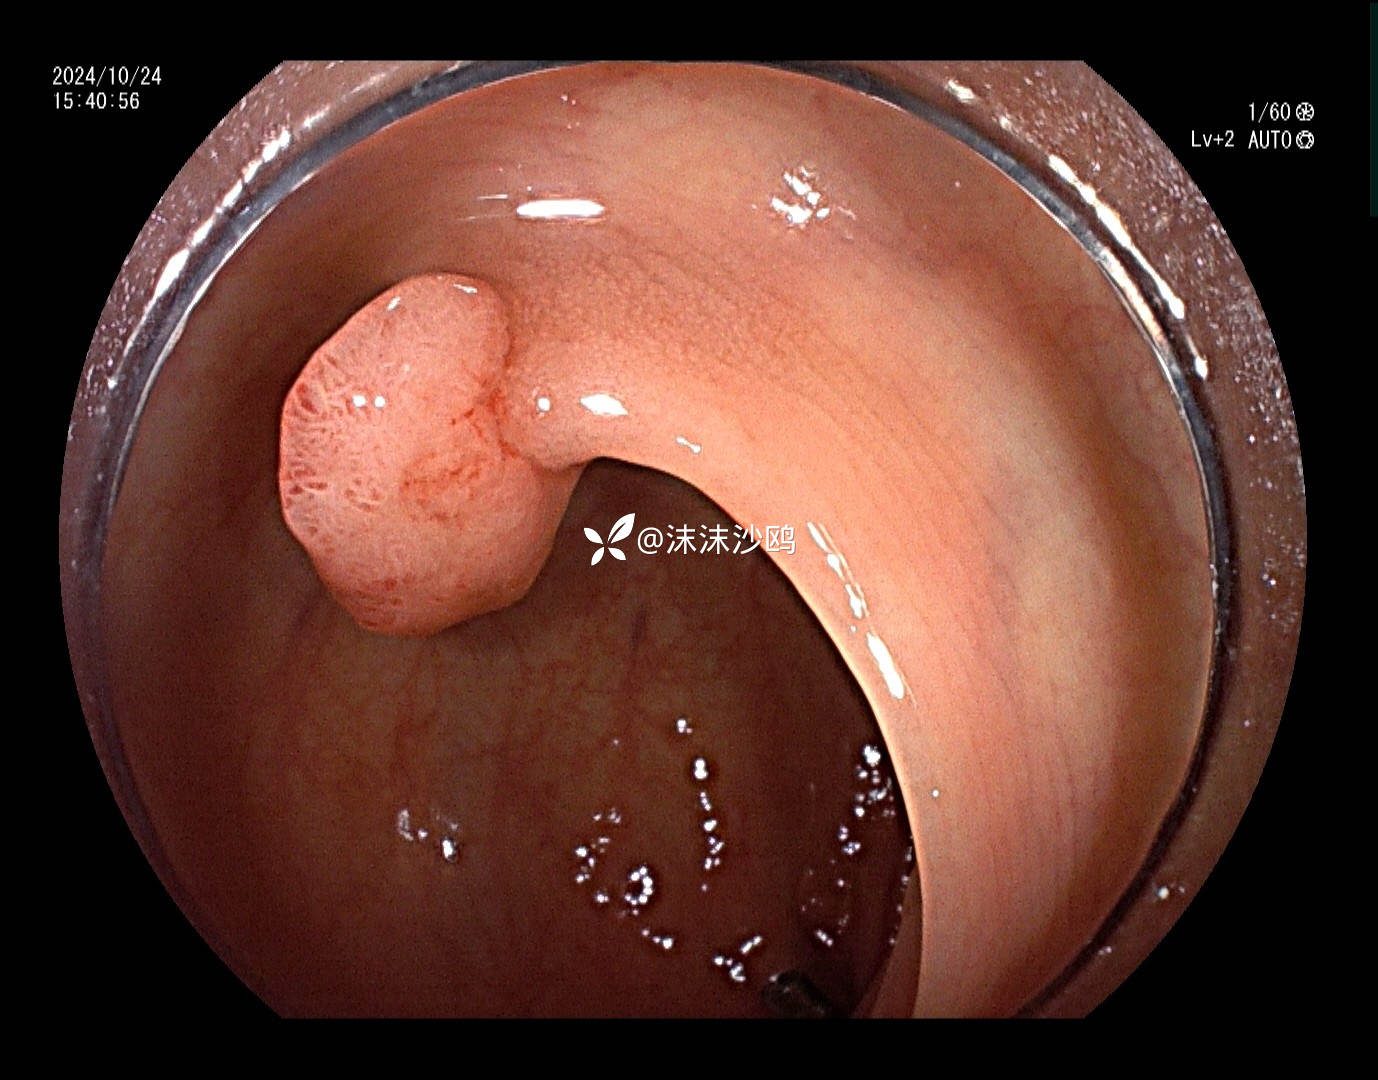

患者去年发现乙状结肠肿瘤同是发现多发腺瘤样隆起,先做了肿瘤切除手术,没有进一步放化疗,现来复查肠镜顺便嘎息肉。翻看之前的肠镜报告,肠道清洁差,发现的息肉就有六七个,应该还有漏掉的。嘱患者肠道一定要清洁到位。今日下午只安排了他一个人的肠镜专场,专门处理他的息肉。

冰山一角,大大小小嘎了十三四个,大的就有六七个,大部分EMR切除。希望术后不要有并发症。